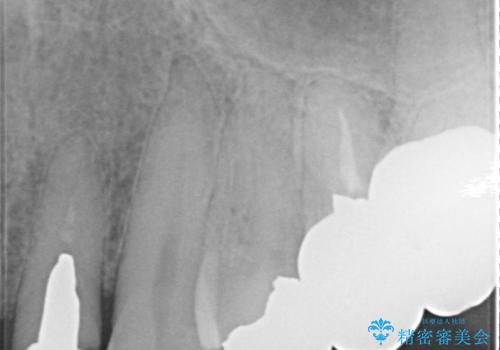

レントゲンを撮影すると、適合不良のかぶせ物が装着されており、根の治療も不十分であることが確認されました。